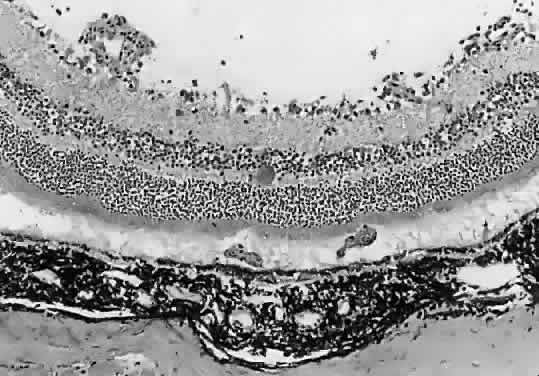

The lesions of ocular toxoplasmosis (Fig. 1) can be important causes of blindness, particularly if they involve the macula, the papillomacular bundle, or the optic nerve. Occasionally, a large peripheral lesion casts off so much inflammatory material into the overlying vitreous humor that vision is affected. In some cases, inflammation initiates organization of the vitreous body; on subsequent contraction of the fibrous bands within this inflammatory mass, tearing of the retina may occur and retinal detachment may ensue.

Fig. 1. The characteristic lesions of toxoplasmic retinochoroiditis in the fundus of an adult. Black arrow denotes active lesion with indistinct borders. White arrow denotes healed “satellite lesions.” (O'Connor GR: Ocular toxoplasmosis. In Locatcher-Khorazo D, Seegal BC (eds): Microbiology of the Eye. St Louis, CV Mosby, 1972.)